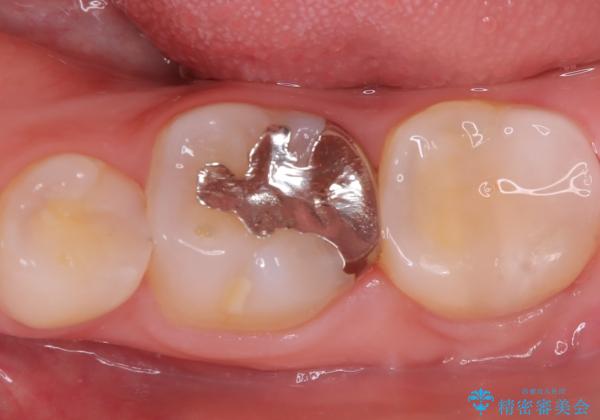

- 初診時にお口の中をチェックしたところ虫歯があり、大きさから部分的な詰め物のお話をしました。材料の特性を説明し、再び虫歯になりにくいセラミックインレーを選択されました。

セラミックインレー接着時にはラバーダム防湿を行いました。